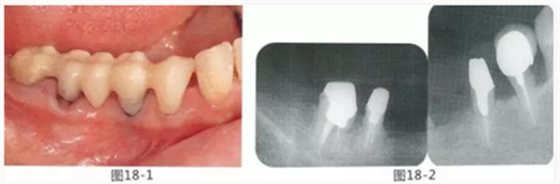

圖18-1 右上4,5,6,6,7部位,初期治療結(jié)束時牙齦的狀態(tài)。

圖18-2 手術(shù)前同部位的口腔X光片。